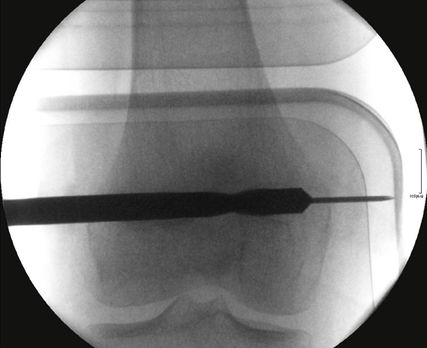

Verschiedene technische Verfahren wurden zur permanenten Epiphyseodese publiziert (z.B. Phemister, Canale). Canale beschrieb ein Verfahren zur perkutanen minimalinvasiven Anbohrung der Wachstumsfuge von medial und von lateral, welche sich als Standardmethode zur permanenten Wachstumsbremsung etabliert hat (Abb. 1). Canale fordert dabei die Anfertigung eines „bull-eye“ von medial und von lateral, welches im seitlichen Strahlengang die Fuge überschreitet, um eine ausreichende Zerstörung des Wachstumsknorpels sicherzustellen (Abb. 2). In einer rezenten Publikation wurde empfohlen, das Bohrloch in der Frontalebene auch über die Mittellinie zu führen, um eine unvollständige Epiphyseodese und damit ein Restwachstum zu vermeiden.